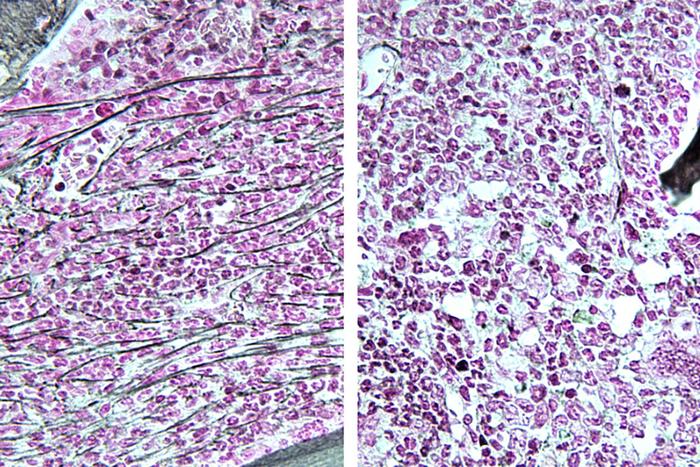

In the Nature Communications study, inhibiting RSK1 helped reverse the progression of MPNs in mice, reducing fibrosis, or scar formation, in the bone marrow. Inhibiting RSK1 eliminated up to 96% of cancer in mice after four weeks. It also showed evidence of preventing the chronic disease from transforming into secondary AML.

In the Blood Cancer Journal study, blocking this protein treats a specific form of AML called FLT3-ITD AML that develops directly — without an MPN developing first. This type of AML can be treated with established drugs called FLT3 inhibitors, but the cancer often develops resistance to this treatment over time. Because the RSK1 inhibitor blocks a different pathway, Oh and his co-authors suggested, it could help address this resistance.